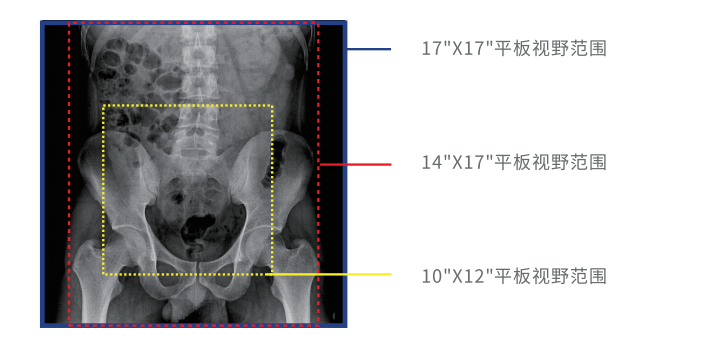

大幅面高清成像

動態(tài)DR采用17 英寸×17 英寸方形動態(tài)成像,臨床操作醫(yī)生可以在一個大幅面下觀察診斷,當(dāng)看到病變部位時,配合實時點片技術(shù),能夠很好地捕捉到病變點,也大大縮短了檢查時間,與圓形成像的傳統(tǒng)胃腸機相比在臨床上具有巨大優(yōu)勢。